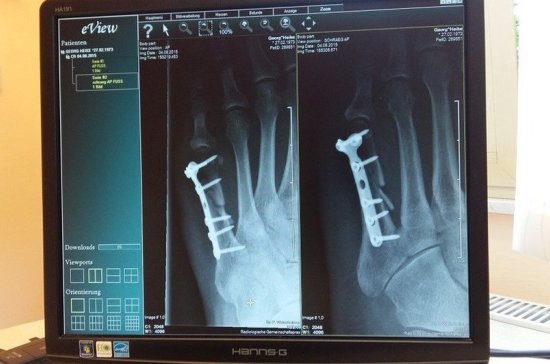

Новые цифровые рентген-аппараты были установлены в больницах Солнечногорска в рамках нацпроекта «Здравоохранение». Устройства позволяют получить более качественную картинку и безопаснее для пациентов, рассказала заведующая рентгенологическим отделением Солнечногорской центральной районной больницы Елена Табелева, сообщает телеканал «360».

«Новые цифровые аппараты позволяют более качественно работать и получать снимки с высоким разрешением при минимальной лучевой нагрузке на пациента», — отметила главврач.

Плюсом новых аппаратов является то, что они интегрированы в единую медицинскую информационную систему. Снимки туда загружаются автоматически и хранятся в единой базе данных.